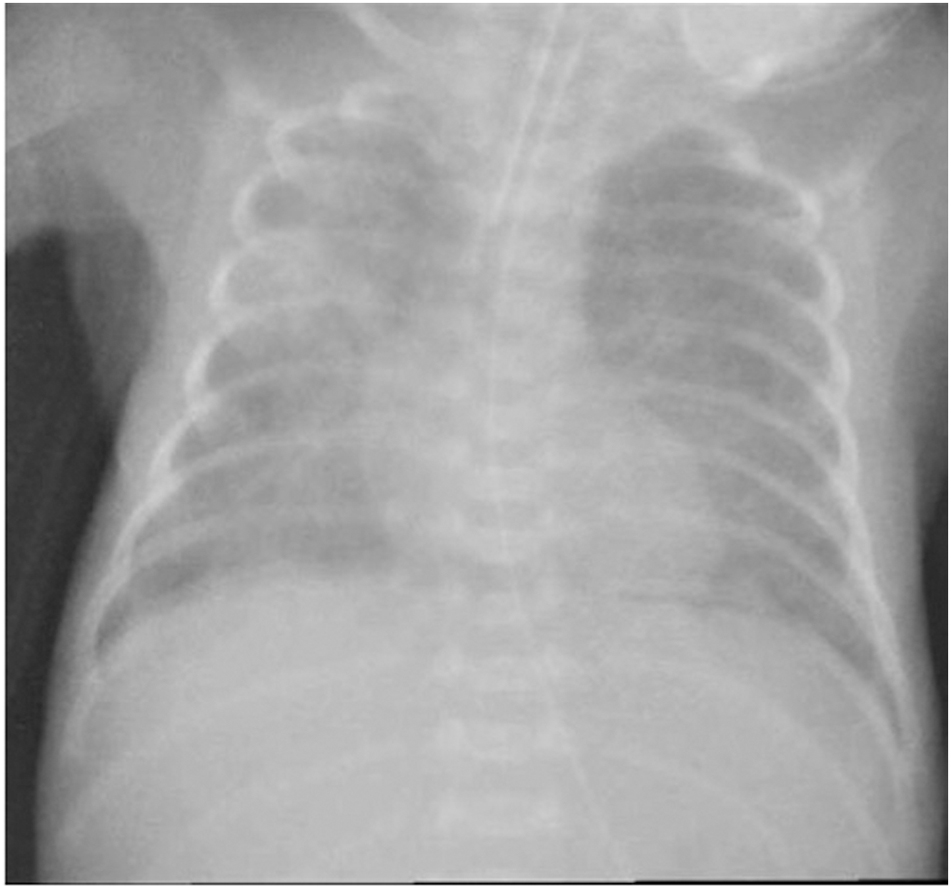

A 38-year-old woman (gravida 1, para 0) with threatening preterm labour was admitted to our hospital at 24+1 weeks’ gestation. The pregnancy was the result of “in vitro” fertilisation. Two doses of betamethasone were administered at the time of admission. The woman delivered a baby girl at 25 weeks and 1 day of gestation by spontaneous vaginal delivery. The baby was intubated in the delivery room for apnoea and admitted to our level III NICU for further management. Apgar scores were 5 at 1 min, and 7 at 5 min, respectively. Growth parameters at birth were: weight 750 g (72nd centile), length 33 cm (72nd centile) and head circumference 22.8 cm (36th centile). A chest radiograph revealed severe hyaline membrane disease. Surfactant, 200 mg/kg (Curosurf®, Chiesi Pharmaceutical, Parma, Italy), was administered and mechanical ventilation was initiated. After obtaining specimens for blood culture, empirical treatment with ampicillin and gentamicin (GEN) was started. The first blood culture was sterile at 48 h and C-reactive protein (CRP) was <0.5 mg/dL (normal value <0.5 mg/dL), therefore ampicillin and GEN were discontinued. On the 5th day of life, oxygen requirement increased, and a hemodynamically significant patent ductus arteriosous (PDA) was diagnosed. A course of ibuprofen was administered and a repeat echocardiogram confirmed the closed PDA. Extubation was unsuccessfully attempted on postnatal day 7. The following day, the baby started to show clinical decompensation with increasingly frequent desaturations, and decreased gas exchange. Conventional mechanical ventilation was shifted to high frequency oscillatory ventilation (HFOV). The peripheral white blood count was 32 x 109/L (neutrophils 0.58), the CRP level was 3.48 mg/dL, and the procalcitonin level 7.4 mg/dL (normal value <0.5 mg/dL). Blood and bronchoalveolar lavage (BAL) for analysis and culture were obtained and therapy with oxacillin (OXA) and GEN was initiated. Lumbar puncture was not performed because of the baby’s severe respiratory status. Echocardiography revealed no residual ductal shunting. Pulmonary X-ray showed asymmetric multifocal areas of opacity bilaterally (Figure 1). After 10 h of incubation, a blood culture bottle was flagged as positive and Gram staining showed Gram-negative rods. OXA was discontinued, and piperacillin-tazobactam (TZP) was added while awaiting culture identification and sensitivity. The central venous catheter was immediately replaced in order to eradicate the catheter-related bacteraemia. Blood culture and BAL samples demonstrated a VIM-producing KP. The isolates were susceptible only to tigecycline and colistin and resistant to aminoglycosides, fluoroquinolones and all the β-lactam antibiotics tested (Table 1). Species identification and antimicrobial susceptibility testing were performed using VitekMS matrix assisted laser desorption ionization-time of flight (Maldi-TOF) (bioMerieux, Craponne, France) and Vitek2 (bioMerieux), respectively. Molecular identification of the carbapenemase gene was obtained by Xpert Carba-R (Cepheid). As the baby’s laboratory tests and clinical condition had improved at first the antibiotic treatment was not changed based on the antibiogram. On day 5 of therapy, the respiratory status deteriorated and the patient developed severe hypoxaemia and hypercapnia despite maximal ventilatory support. A chest radiograph revealed an extensive airspace infiltration in the right middle and lower lobes. A dishomogeneous consolidation also involved the left upper lobe (Figure 2). As shown in the antibiotic timeline (Figure 3), the initial antibiotic regimen was modified to meropenem (MEM) (60 mg/kg dose infused intravenously over 6 h, 4 times a day) plus GEN. Additionally, aerosolised GEN (0.6 mg in 2 mL of normal saline 4 times a day) was administered by means of a nebuliser. The new treatment led to a rapid improvement in the patient’s respiratory status and clearing of the strain of K. pneumoniae from the patient’s BAL. She completed 2 weeks of intravenous GEN and 10 days of MEM and nebulised GEN, with good results. Trough serum level of GEN was monitored, and was consistently in the therapeutic range. Complete blood count, serum creatinine and electrolytes were tested every 3 days, and transaminases were evaluated weekly during antibiotic administration. Based on these tests, there was no evidence of any biochemical or haematological toxicity resulting from the treatment. The infant was extubated at day 32 of life. After extubation, the baby remained on nasal continuous positive airway pressure (NCPAP) for a total of 8 days. Respiratory support (high-flow nasal cannula therapy) was withdrawn completely at 37 weeks and 6 days post-conceptional age, and she started oxygenating well in room air. Sequential ultrasound examinations, including at discharge, did not detect any abnormal findings. There was no severe retinopathy of prematurity, only stage 2 in zone III without plus disease. She was vaccinated and sent home on day 96, weighing 2170 g, with a head circumference of 32 cm, and a length of 43 cm. During hospitalisation, VIM-producing KP was persistently detected in surveillance rectal swabs, but not from other sites. Contact isolation was maintained until the time of discharge from the hospital. A rectal swab obtained from the mother did not show any carbapenemase-producing Enterobacteriaceae ruling out the possibility of mother-to-child transmission at birth.

Chest radiograph, 8 days of age, showing asymmetric multifocal areas of opacity.